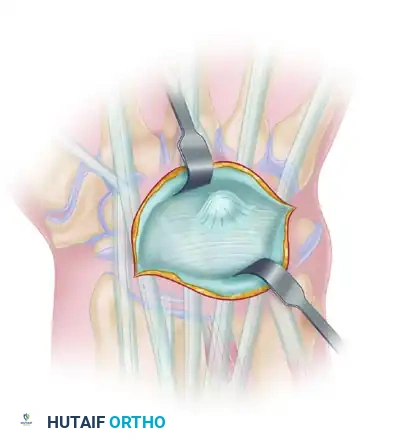

2. Joint Preparation: The Cup-and-Cone Technique

Achieving a high union rate requires maximizing the cancellous bone contact area. The "cup-and-cone" technique is highly recommended as it provides intrinsic stability and allows for fine-tuning of the thumb position before definitive fixation.

- Metacarpal Preparation (The Cone): Use a rongeur and an air-driven burr to remove the remaining articular cartilage and dense subchondral bone from the base of the first metacarpal. Shape the base into a convex, cone-shaped surface of healthy, bleeding cancellous bone.

- Trapezial Preparation (The Cup): Use a high-speed burr, curet, and small osteotomes to shape the distal articular surface of the trapezium into a concave cup configuration. The radius of curvature must match the metacarpal cone perfectly.

Appose the prepared bone surfaces and assess the fit. The cup-and-cone geometry allows the surgeon to rotate and angulate the metacarpal into the perfect functional position without losing bony contact.